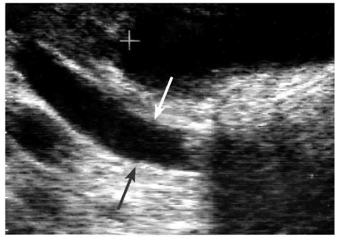

- אולטרה-סאונד של דרכי המרה (תצלום 49.8).

- EUS - של דרכי המרה. נראה הרחבה של דרכי המרה ואת הגוש החוסם.